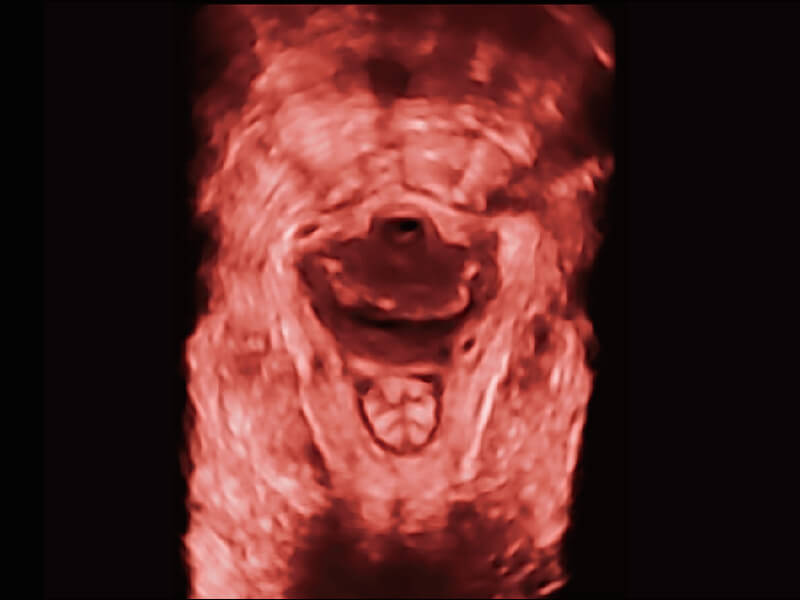

成像功能

S60探头工艺,从前端信号处理每一个环节采集无损声学数据,真实还原组织原貌,再现解剖细节。

超宽频带技术,为容积成像带来优质的二维图像基础,为您呈现丰富的结构细节,栩栩如生地展示宝宝的宫内形态以及各种组织的立体结构。